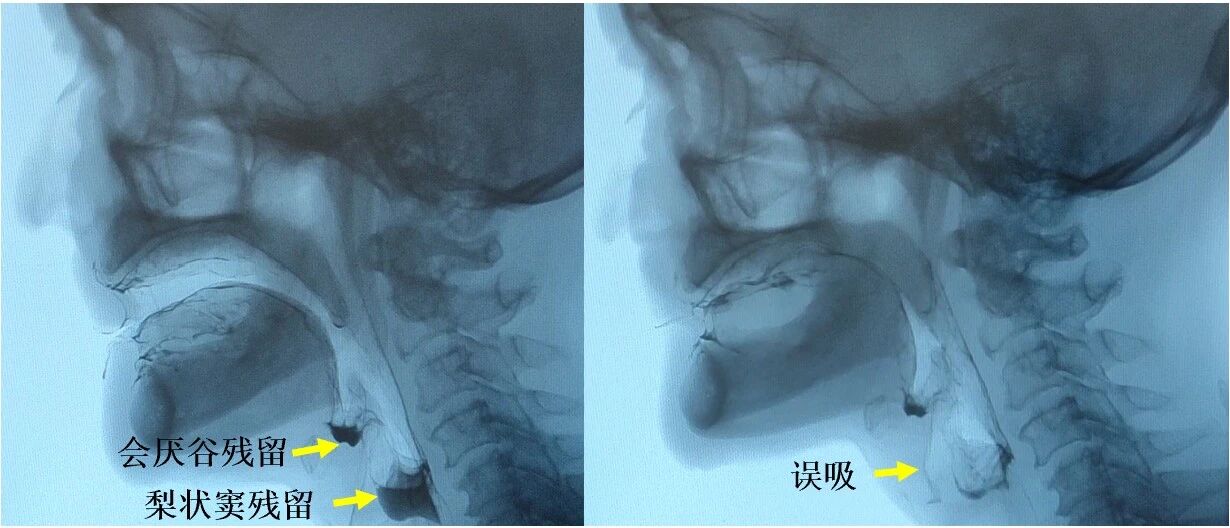

咽缩肌的病理组织改变的减轻最终在功能效应层面表现为咽缩肌功能的显著改善。造影检查显示,对比标准放疗组,内侧组咽后区豁免放疗组中出现会厌谷残留(74% vs. 100%;P<0.001)、梨状窦残留(48% vs. 73%;P=0.01)、咽后壁残留(11% vs. 27%;P=0.01)、咽通过时间>1.0秒(2% vs. 11%;P=0.03)及误吸(12% vs. 29%;P=0.03)等咽期受损表现的频率均更低。

图4:造影检查所示会厌谷残留、梨状窦残留及误吸